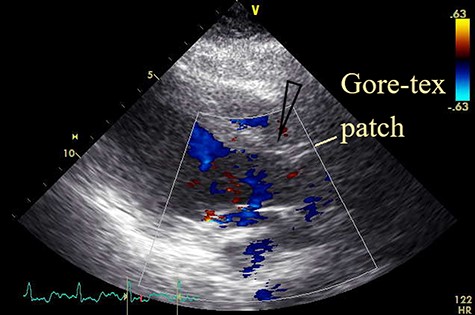

Postoperatively, the patient required prolonged intensive care. Inhaled nitric oxide for 3 days and continuous veno-venous hemofiltration for 10 days supported the patient and significantly improved blood parameters, which gradually normalized in the following days. A postoperative TTE revealed no shunt or aortic regurgitation (Fig. 3). However, a tracheostomy was performed on postoperative day (POD) 15 because of prolonged ventilation. The patient was discharged on POD 55 in a stable condition after de-cannulation of the tracheostomy tube.

Postoperative transthoracic echocardiogram; the view after patch closure by Gore-tex® 0.4-mm patch with no shunt flow (open arrowhead).